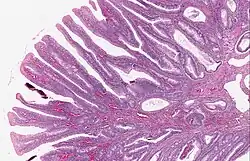

Micrograph of a villous adenoma. These polyps are considered to have a high risk of malignant transformation. H&E stain. -

| Villous adenoma | 15%[16] to 40%[15] | Over 75% villous[14] |

The villous subdivision is associated with the highest malignant potential because they generally have the largest surface area. (This is because the villi are projections into the lumen and hence have a bigger surface area.) However, villous adenomas are no more likely than tubular or tubulovillous adenomas to become cancerous if their sizes are all the same.[18]

- Villous adenoma: 40% risk of cancer